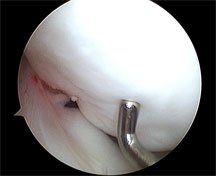

If you look on the right at the first of the photos taken during arthroscopy, you can see the shiny probe pressing into the overlying joint cartilage. It is clear that it is softened, allowing the rounded probe to dimple its surface. Normally the cartilage is quite firm and does not allow this dimpling.